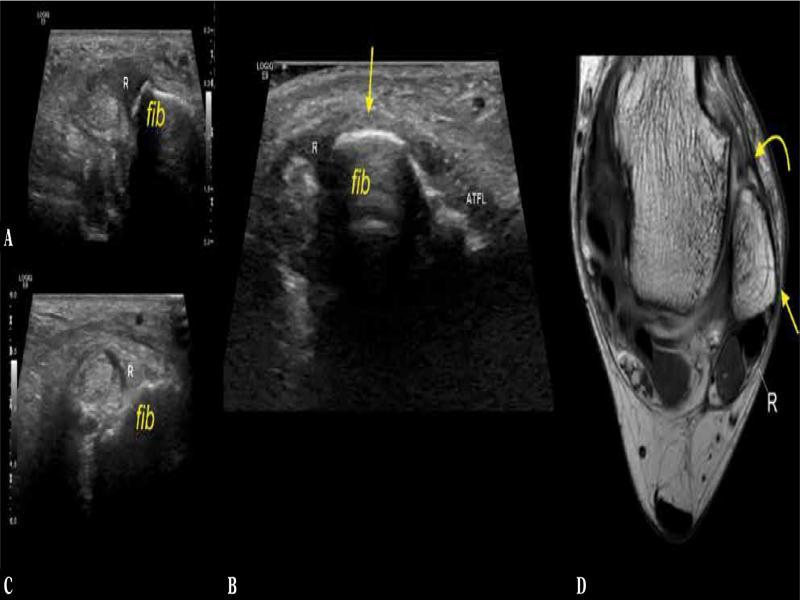

Fig. 7.

Anatomical variations of the peroneal tubercle, three different patients. A, B, C. coronal sections, ultrasound, A. no explicit peroneal tubercle was noted (X), B, C. the peroneal tubercle (t) was present. The peroneus brevis (curved arrow) and the peroneus longus (dashes curved arrow)

In most cases, the peroneal tubercle was found both on US and CT (65.1% and 63.5%, respectively) (Tab. 2, Fig. 8); however, no hypertrophy of the peroneal tubercle was observed. US showed the peroneal tubercle presence in 1.6% cases more compared to CT (p <0.05). We identified 6 cases (9.5%) with os peroneum present on CT while only 3 (4.8%) of them were detected on US (p >0.05). Low-lying peroneus brevis muscle belly was identified in 7 cases (11.1%) on US and in 5 cases on CT (7.9%), p <0.05. No case of peroneus quartus or tertius muscle was found.

Fig. 8.

The most common variant of the retromalleolar fibular groove, convex (straight arrow). A 39-year-old patient with a suspicion of rheumatoid arthritis. A, B. cone-beam computed tomography ( A. 3D posterior medial view, B. transverse section), C. transverse ultrasound section. SPR (curved arrow) was connected (dashed curved arrow) to IER (not shown). Fib – the lateral malleolus